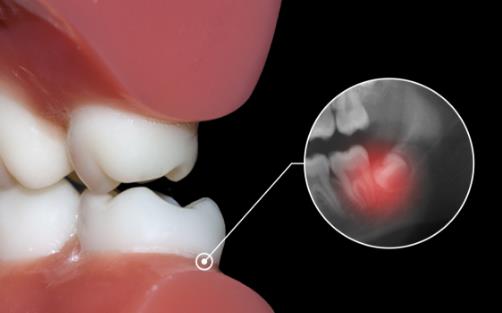

智齒是一個很常見的口腔問題,從現(xiàn)代醫(yī)學的觀點看,由于人類食物日益精細,而使用牙齒的磨耗日益減少及咀嚼刺激降低等原因,智齒是人類進化中退變的必然 。一旦出現(xiàn)智齒,就需要及時拔除,避免其對口腔造成危害 。對于智齒的拔除一般分為兩種情況,一是治療性拔除,一是預防性拔除 。下面和一起來看看吧 。

阻生的智齒牙冠周圍軟組織與牙齒之間形成一盲袋,引起食物、細菌的積存,抵抗力下降時,出現(xiàn)冠周炎是必然的 。一般的消炎治療治標不治本,因此冠周炎會反復發(fā)作 。

位置不正的智齒與第二磨牙之間容易積存食物殘渣,而且不易清潔,一般數(shù)月可形成齲齒,直接破壞牙體組織 。